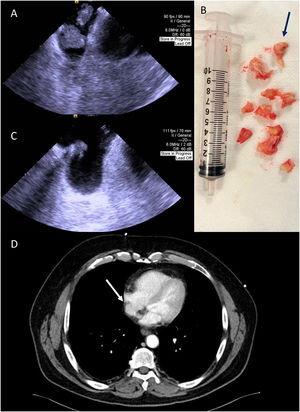

Intracardiac echocardiography (ICE) was selected to guide mechanical aspiration with the FlowTriever 24Fr System,1 as it obviates the need for transesophageal echocardiography, which may carry sedation-related hemodynamic risks.2 It was possible to remove the shorter mass and almost the totality of the larger mass, that was severely attached to the terminal part of the TIVAP (Figure 2, Panels A and B and Supplementary Videos 1–3). At the end of the procedure, a pulmonary angiography did not reveal significant perfusion defects or pulmonary hypertension. ICE showed residual thrombus attached to the terminal part of TIVAP, confirmed by CT angiography (Figure 2, Panels C and D), which also revealed fragmental thrombus in the lower lobe of the left pulmonary artery. Histological analyses confirmed the presence of chronic organized thrombus. The post-procedure course was free of complications, and the patient was discharged after four days. Anticoagulation was maintained.

Panel A: Intracardiac echocardiography used to guide mechanical aspiration showing the two masses. Panel B: The fragmented thrombus that was aspirated from the right atrium – predominantly white, compatible with the presence of fibrin (blue arrow). Panel C: Post-procedural intracardiac echocardiography image demonstrating a residual thrombus. Panel D: Thoracic CT angiography performed after the procedure showing small residual thrombus in the right atrium (white arrow).